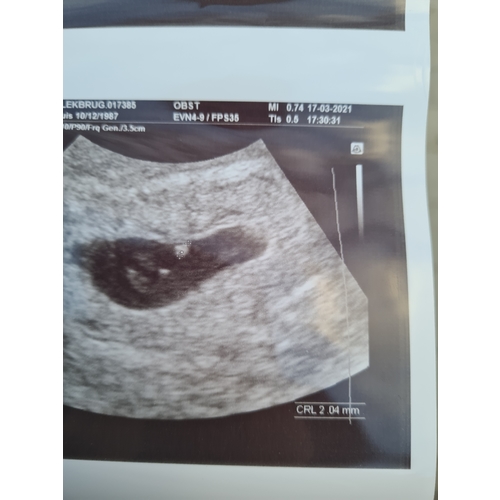

Ik had 10 maart eerste echo. Volgens eigen berekening had ik 8+2 moeten zijn. Helaas ook een leeg vruchtzakje. Vorige week 17 maart moest ik terug komen en toen zag ze een frummeltje. Ze kon nog niks zeggen. Moet volgende week woensdag weer terug komen. Ik was 11 januari ongesteld geworden tot 17 januari. Daarna had ik 4 en 5 februari licht roze bloed verlies. Ik dacht innestelingsbloeding. Had 8 en 9 februari lichte positief getest.

Tweede echo met het frummeltje